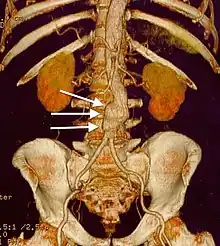

| CT reconstruction image of an abdominal aortic aneurysm (white arrows) | |

Abdominal aortic aneurysm (AAA) is a localized enlargement of the abdominal aorta such that the diameter is greater than 3 cm or more than 50% larger than normal.[1] An AAA usually causes no symptoms, except during rupture.[1] Occasionally, abdominal, back, or leg pain may occur.[2] Large aneurysms can sometimes be felt by pushing on the abdomen.[2] Rupture may result in pain in the abdomen or back, low blood pressure, or loss of consciousness, and often results in death.[1][6]